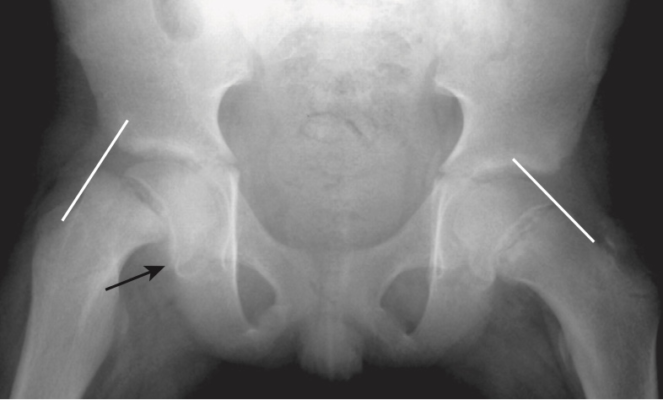

Gãy cổ xương đùi ở người già

- Thường gặp và thường liên quan đến loãng xương

- Chụp X quang cổ xương đùi thường quy nên được thực hiện với chân của bệnh nhân ở tư thế xoay trong để hiển thị cổ ở dạng trực diện. Tìm dấu gập góc của vỏ xương hoặc các vùng có tăng đậm độ chứng tỏ có sự chồng lấn (Hình 19).

- Đôi khi gãy cổ xương đùi có thể rất khó nhận biết và cần phải chụp MRI hoặc scan xương bằng phóng xạ hạt nhân để chẩn đoán.